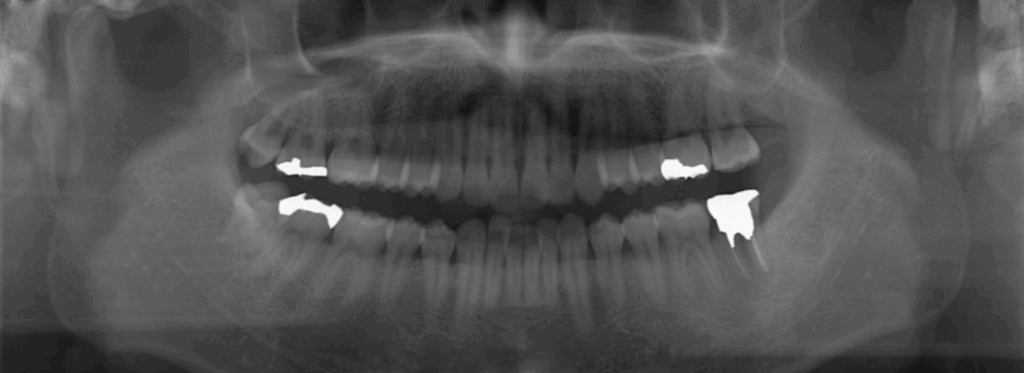

術前レントゲン写真

左下7の歯根破折を伴う重度歯周炎

CTにて根尖性歯周炎の併発も確認

術前 移植に際してレントゲンではCT程の情報量がなくそもそも抜歯適応なのか判断に苦慮する